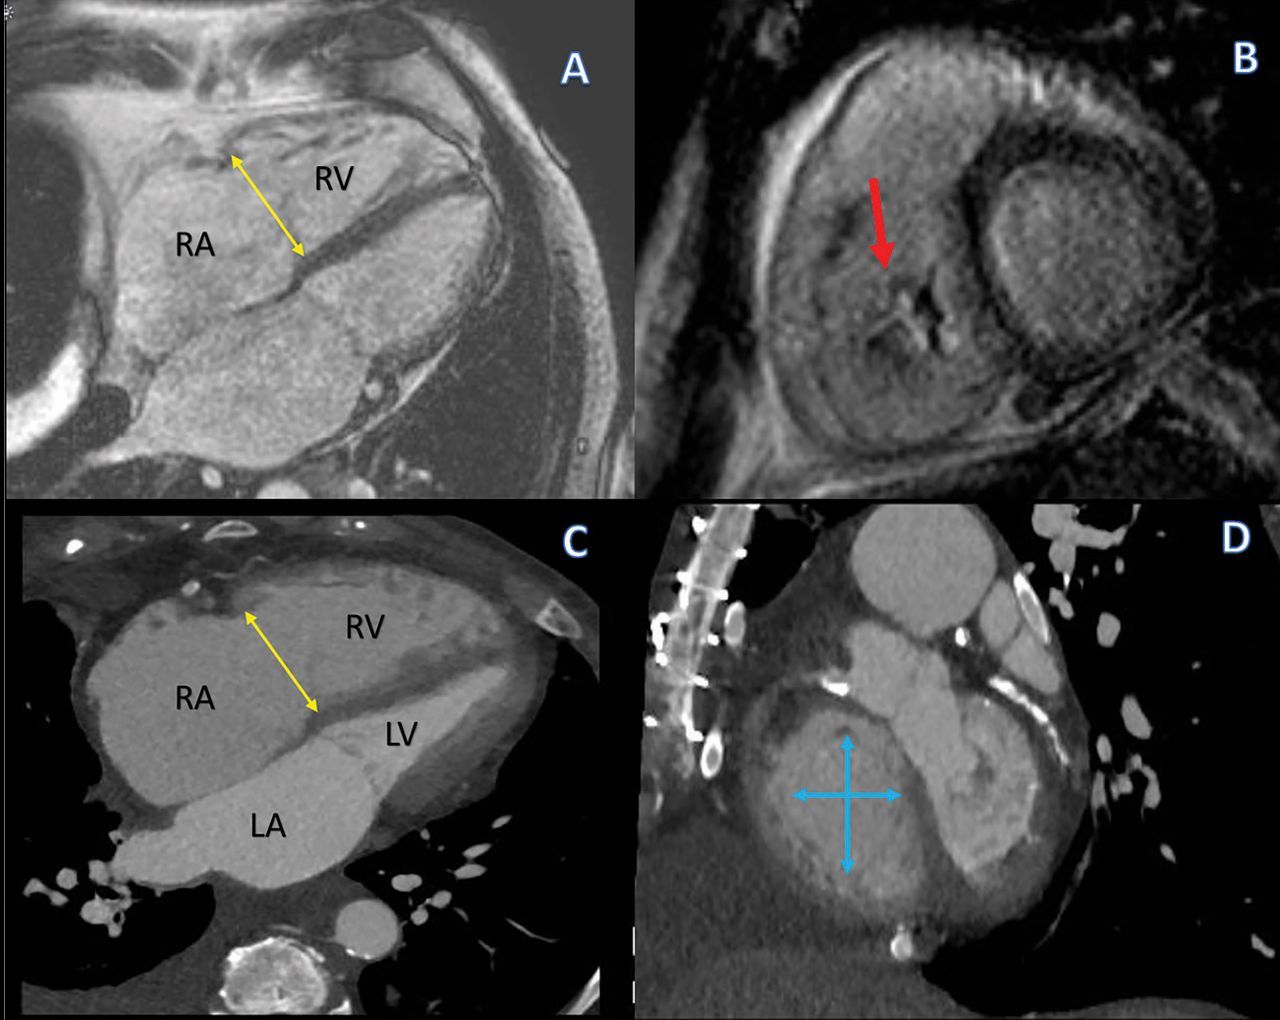

moderator band in which compartment?

RV

moderator band connects which structures?

IV septum anterior papillary muscle